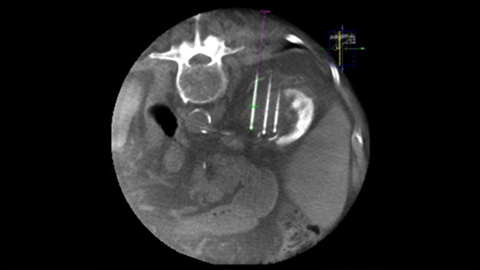

Dual View allows the overlay of a pre-procedure 3D image (CT/MR/PET-CT) on an intra-procedure 3D CBCT to better visualization the lesions and access critical input for needle planning [8].

XperGuide Ablation displays the virtual needle path to assist in multiple needle planning. It shows needle characteristics such as ablation zone/isotherm to confirm complete tumor coverage prior to ablation.

With CBCT acquire a post-ablation CBCT to demonstrate the extent of tumor coverage and confirm completeness of your treatment.